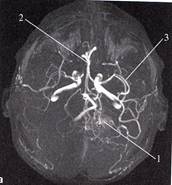

1. Определите метод лучевой диагностики и плоскость исследования.

2. На предыдущих снимках определите анатомическую область применения метода лучевой диагностики.